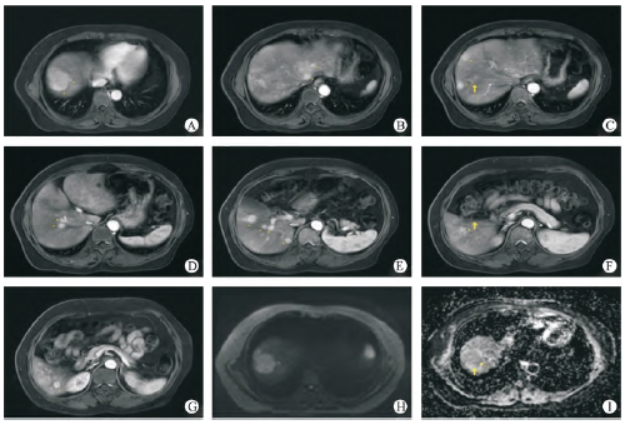

患者女性,53 岁,在体检时发现肝内多发结节(约14个),较大者位于肝右叶S8 段,大小约4.2 cm × 5.2 cm ×2.9 cm,多考虑肝癌;肝左叶囊肿(图1)。肿瘤标志物示:AFP 415 IU/mL。行超声引导下肝脏肿物穿刺活检术,穿刺病检示:(肝肿物穿刺活检组织)肝细胞癌,中分化(图2)。

图1 治疗前肝脏多发HCCA - G:在CIRT(2022 - 12 - 02)之前MRI T1增强的不同层面示肝内多发异常强化结节肿块(共14 个),较大者位于肝S8 段,大小约4.2 cm ×5.2 cm × 2.9 cm;H - I:DWI 示弥散受限,ADC 值1.066 mm3 /s。